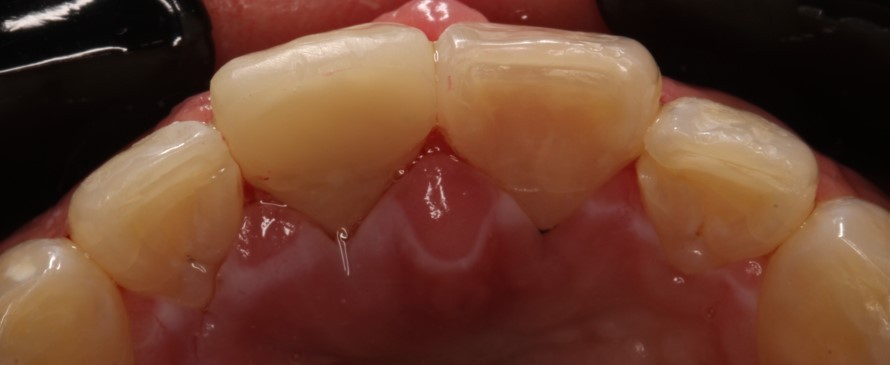

Внутриротовые фотографии 17.10.2022г